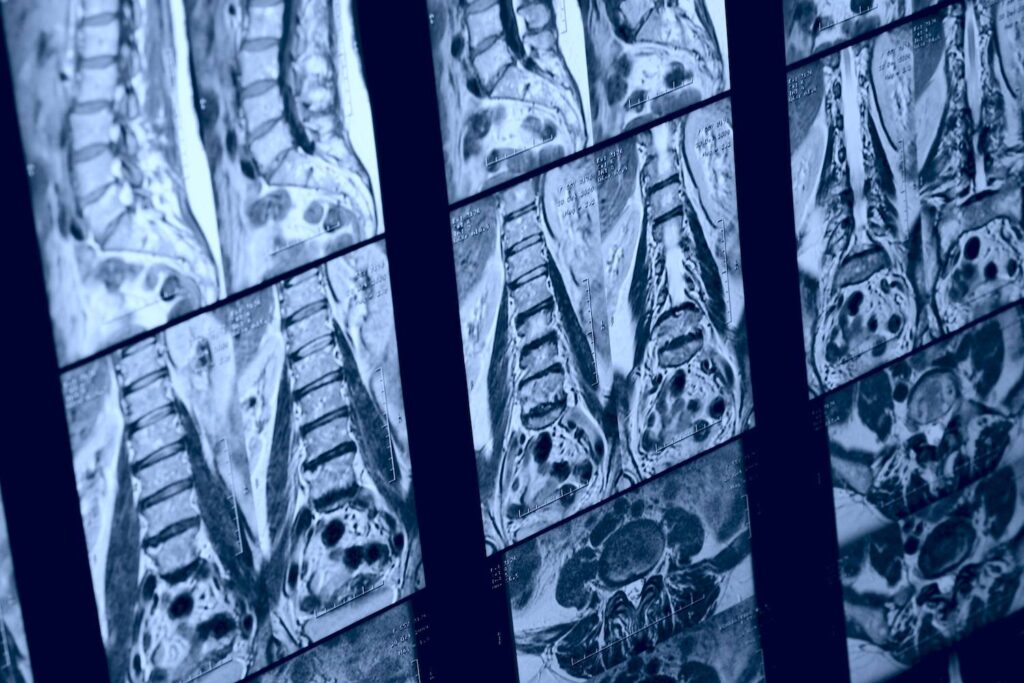

Nach der körperlichen Untersuchung kann der Arzt die Diagnose mit Hilfe von bildgebenden Verfahren wie Röntgenaufnahmen, CT-Scans oder MRT-Scans bestätigen. Es gibt auch Fälle, in denen ein Arzt einen Nervenleitungstest oder eine Elektromyographie durchführen kann, um zu prüfen, ob die Nervenwurzel geschädigt ist. Die häufigste bildgebende Untersuchung zur Diagnose der Erkrankung ist die MRT, die detaillierte Bilder der Weichteile im unteren Rücken liefert.

Die MRT-Untersuchung kann mit einem in die Blutbahn injizierten Kontrastmittel durchgeführt werden, aber das ist nicht immer der Fall. Mit dem Test kann festgestellt werden, welche Bandscheibe betroffen ist, wenn es eine Nervenkompression gibt. Mit dem MRT-Scan können auch Rückenmarkstumore, Abszesse und knöcherne Überwucherungen erkannt werden.